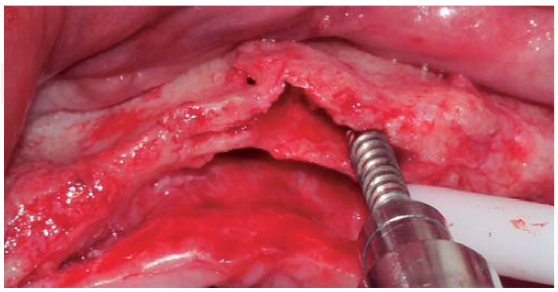

Se realizó una incisión supracrestal a espesor total, elevación del colgajo mucoperióstico exponiendo la tabla ósea hasta 4 mm de la cima de la cresta hacia vestibular y desde ese punto se dividió el colgajo a espesor parcial (Figura 3). Luego se marcaron los puntos de impacto en los sitios designados según la guía quirúrgica para la colocación de los implantes y se iniciaron las perforaciones con una fresa de 1.6 mm de diámetro para determinar el eje y profundidad deseada para los implantes. Luego se procedió a crear un surco a nivel crestal con un disco de diamante rompiendo el hueso cortical para crear el acceso a los escoplos al hueso esponjoso y con éstos se procede a separar las tablas óseas hasta llegar a una profundidad de 5 mm (Figuras 4 y 5). Seguidamente, se continuaron las perforaciones con una fresa de 2.0 mm de diámetro (Figura 6) y se realizó la expansión de la tabla vestibular creando una fractura en tallo verde con los expansores hasta alcanzar el diámetro del lecho óseo suficiente para poder utilizar la última fresa de 3.2 mm de diámetro (Figuras 7 y 8). Posteriormente, se colocaron los implantes a una velocidad de 25 rpm y a un torque de 35 Ncm (Figuras 9 y 10). Seguido de esto, se colocó un injerto óseo bovino particulado (Bonefill® Bionnovation Biomedical, Sao Paulo-Brazil), con la finalidad de preservar la integridad de las tablas óseas vestibulares (Figura 11). Todos estos procedimientos, se realizaron de la misma manera para la colocación de los seis implantes. Finalmente, se suturó con nylon monofilamento 5/0.

Figura 8 Expansor óseo ubicado distalmente en relación con la preparación previniendo una fractura de la tabla vestibular.